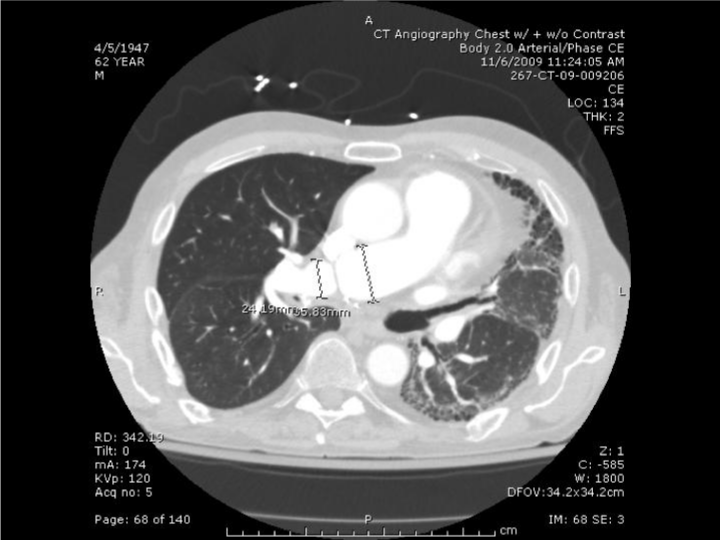

| Figure 5: 62 year old male 3 months following a right single lung transplant for IPF developed dyspnea and hypoxemia. CT angiogram of the chest found focal web-like or shelf-like stenosis in the right pulmonary artery at the level of the anastomosis. The pre-stenotic segment measured 3.1 x 2.9 cm. At the level of stenosis the lumen narrowed to 1.1 x 1.0 cm. Distal to the stenosis, the artery measured 2.6 x 2.2 cm |